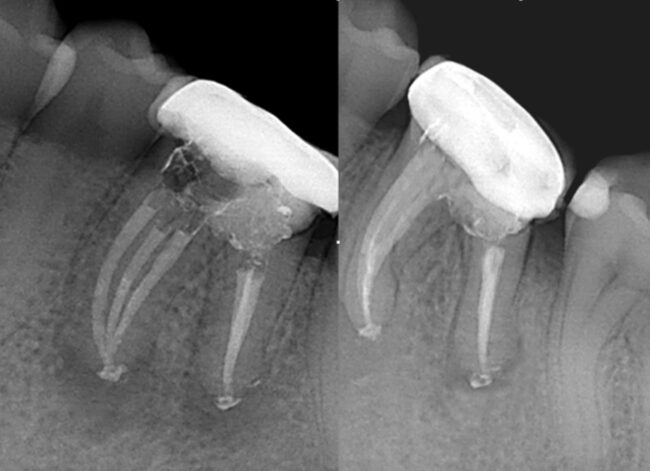

Biopulpectomía en pulpitis irreversible utilizando BlueShaper®, Z-Glider, Fast Pack y Fast Fill

Caso de pulpitis irreversible tratada con los sistemas de instrumentación BlueShaper® y limas Z-Glider ambas de Zarc por el doctor José Conde en su clínica de endodoncia exclusiva, Clínica Conde País.